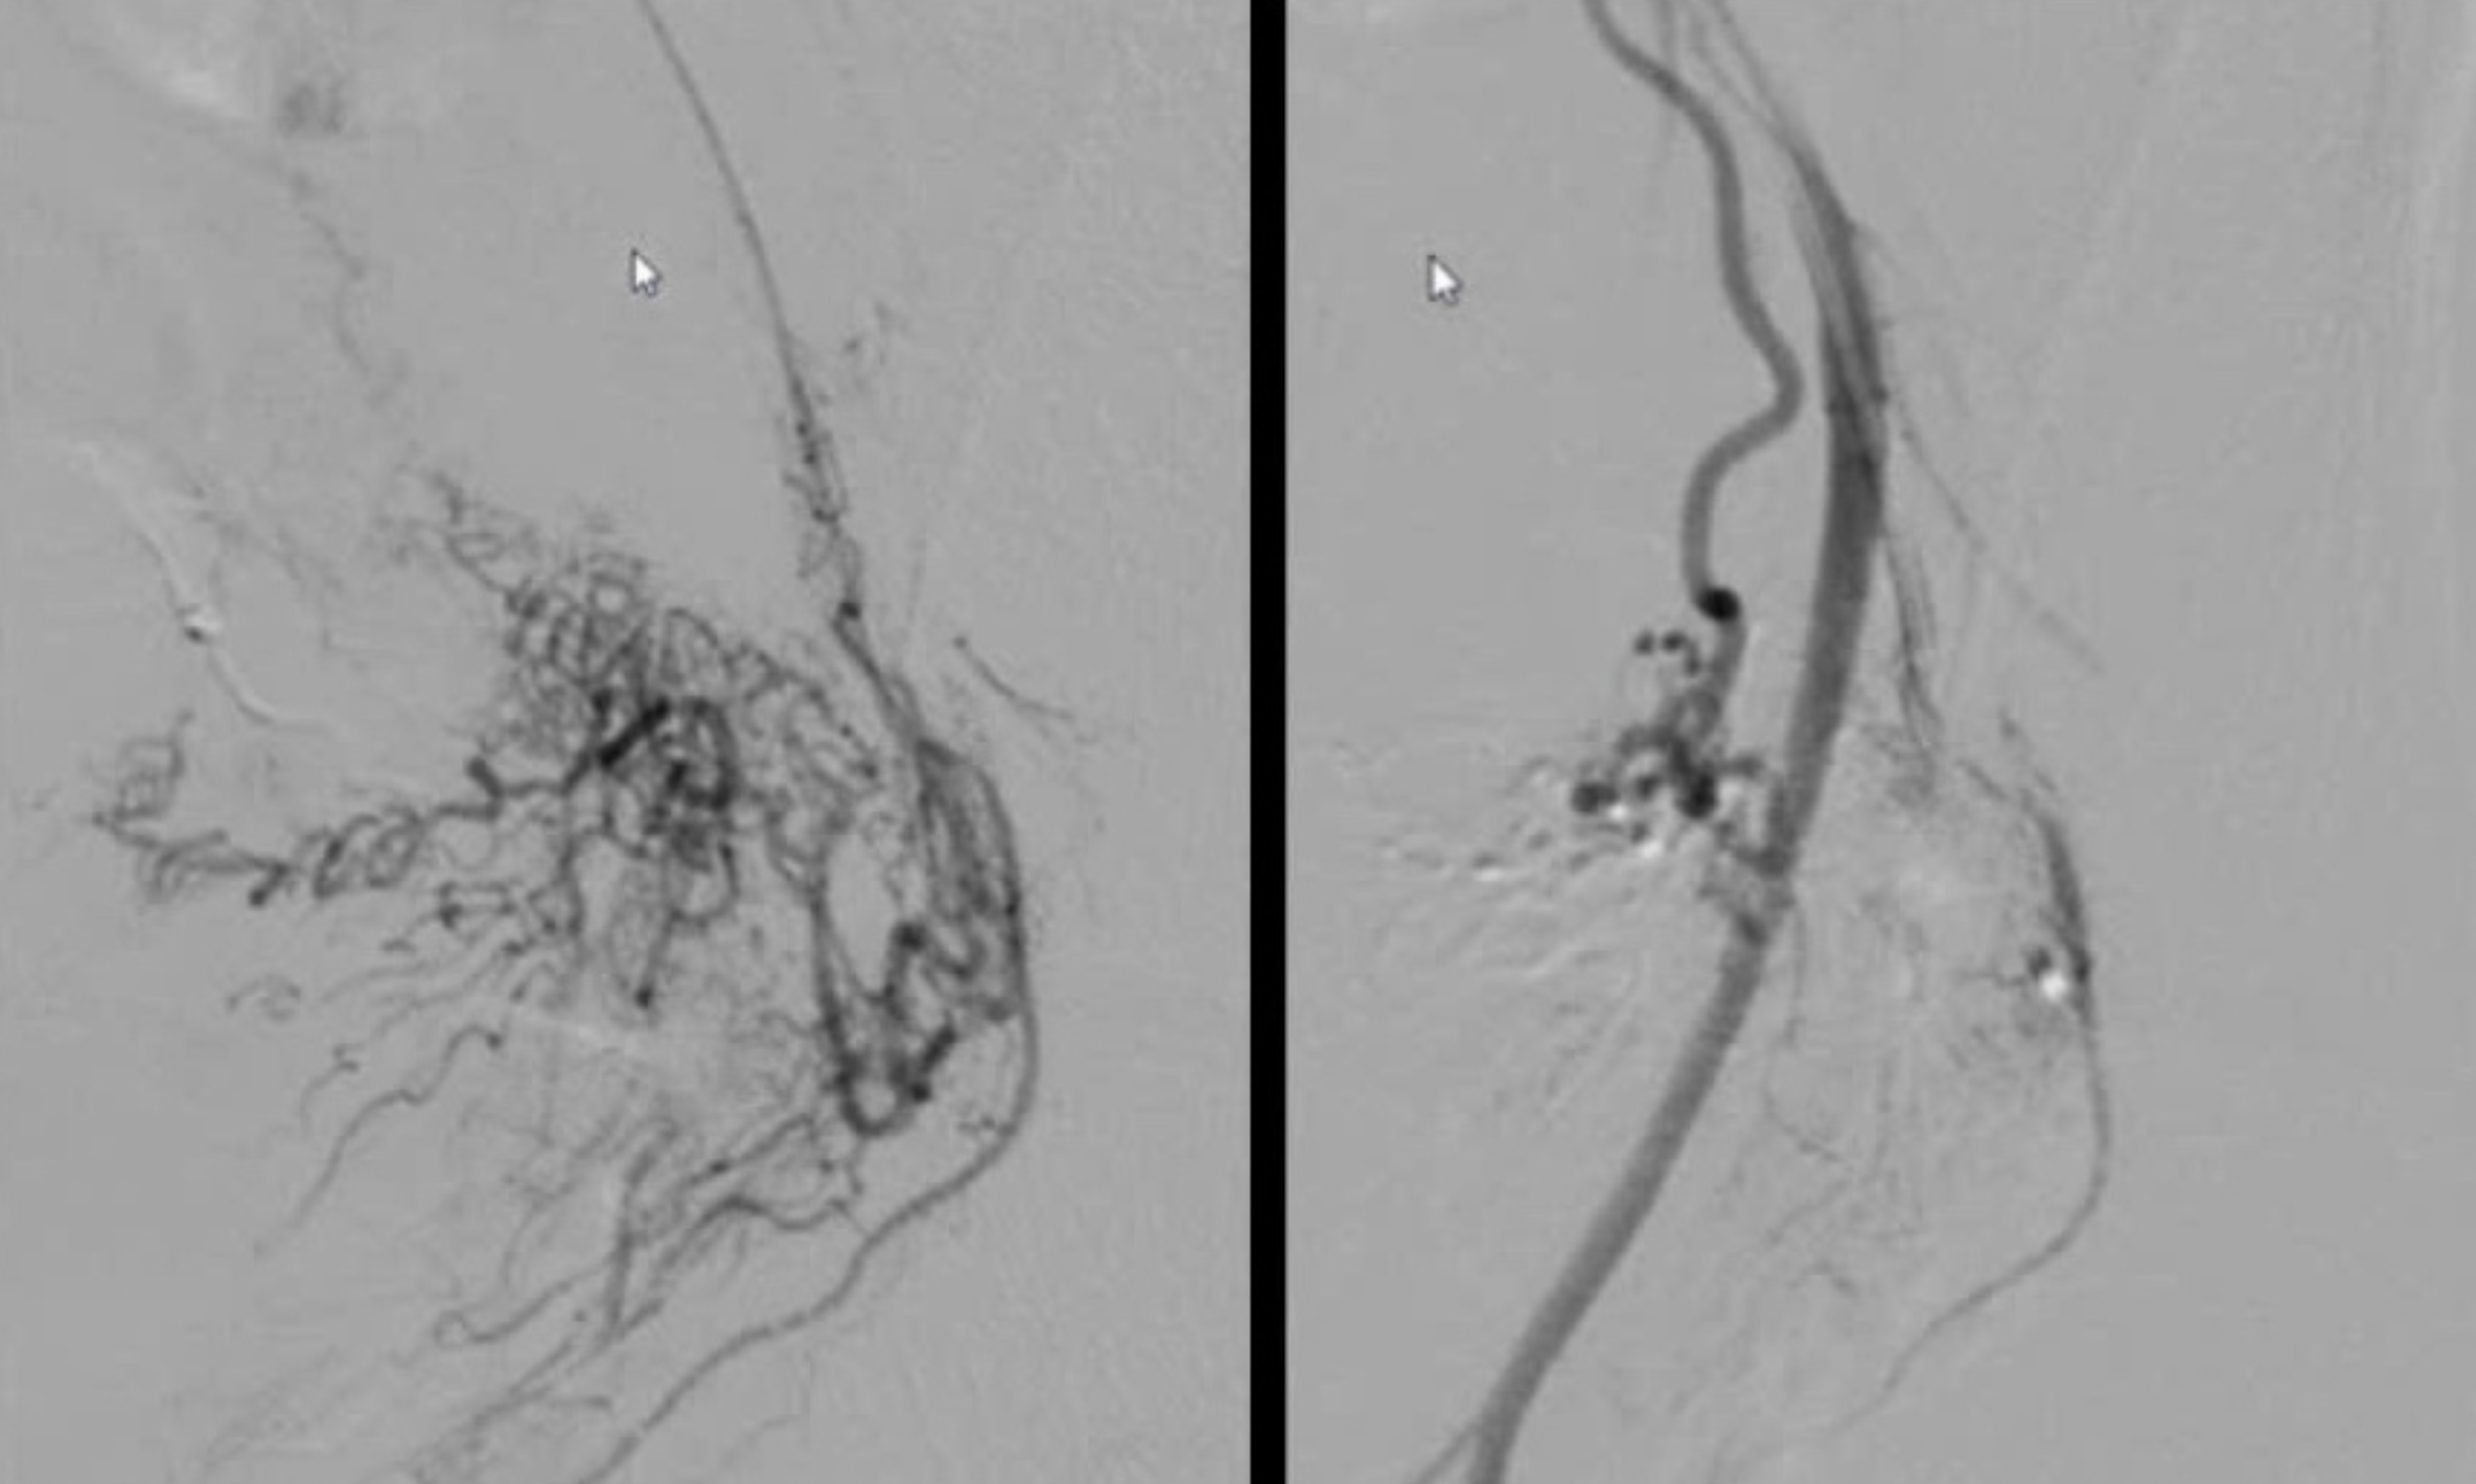

![]() ![]() |

Hình trước và sau khi thực hiện thủ thuật nút mạch tử cung bên phải - trái. |

“Khối u to chèn ép đường đại tiện gây táo bón, ngoài ra khiến bệnh nhân dễ bị xuất huyết nên có hiện tượng rong kinh. Do vậy, sau khi thực hiện thủ thuật tắc mạch, khối u teo nhỏ và không còn chèn ép, theo đó các triệu chứng cũng được cải thiện”, bác sĩ Danh giải thích.

Theo bác sĩ Huỳnh Hữu Danh, tắc mạch được ứng dụng rộng rãi trong điều trị khối u bị tăng sinh mạch máu như u xơ tử cung, u gan, u tuyến tiền liệt, bệnh lý dị dạng mạch máu.

“Đối với u xơ tử cung, phương pháp này được chỉ định trong những trường hợp khối u có kích thước dưới 10 cm, với triệu chứng lâm sàng như đau bụng, táo bón, chảy máu âm đạo”, bác sĩ Danh cho hay.

Mục đích chính của thủ thuật can thiệp nội mạch là làm khối u ngừng phát triển và teo nhỏ, lúc này bệnh nhân có thể sống chung với nó. Ưu điểm của phương pháp là thực hiện nhanh, không cần phẫu thuật, xâm lấn tối thiểu. Nhờ đó, chức năng tử cung vẫn nguyên vẹn sau khi thực hiện thủ thuật, đồng thời cải thiện triệu chứng do u xơ gây ra.